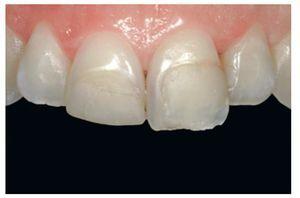

Figura 1 Paciente de 16 años de edad con una restauración deficiente en el diente número 11 y una erupción pasiva evidente.